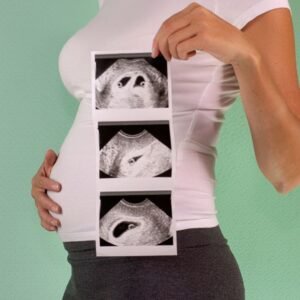

First trimester Nuchal Translucency Ultrasound (11-13 weeks)

A NUCHAL TRANSLUCENCY scan looks at the space at the back of your baby’s neck called the nuchal fold. It is done between 11 and 13 weeks of gestation or when your baby is between 45 mm and 84 mm crown rump length. This is because the fluid behind your baby’s neck tends to get reabsorbed by the body after 14 weeks of gestation.

A higher nuchal translucency measurement may indicate a chromosomal abnormality and/or an increased risk for congenital heart conditions.

The results of the nuchal translucency scan can determine if your baby is likely or unlikely to have these conditions.

Transvaginal Ultrasound with Nuchal Translucency Report + Thermal Prints